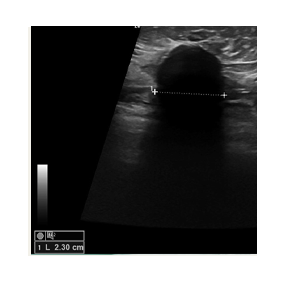

The freezing is achieved with liquid nitrogen  which flows through a probe (needle.) The needle is inserted into the tumor under ultrasound guidance. This allows us to position it very precisely, ensuring that the tumor is at the centre of the freezing zone.

This creates a large ball of ice that engulfs the tumor. By alternating freeze and thaw cycles, the cells in the tumor are destroyed. By the end of the procedure there should be no viable cancer cells left. The progress of ice ball development is closely monitored throughout the procedure to ensure safety.

Ultrasound imaging is used to locate the lesion. The breast is prepared and local anesthesia is given

Using ultrasound guidance, a visica cryoprobe is positioned in the center of the lesion

The cycle is activated and an iceball forms around the tumor. The freezing temperatures destroy the tumor tissue

Freeze and thaw cycles are used sequentially to destroy the tumour